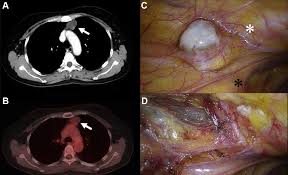

Christiane amanpour is receiving treatment for ovarian cancer. View real ovarian cancer pictures to know what does ovarian cancer look like and gain more knowledge about the disease. Learn more about how to assess your risk, and see memorial sloan kettering's screening recommendations. Pictures show the symptoms, tests, and treatments for ovarian cancer, as well as what factors raise your risk for the disease. Christiane amanpour shares cancer diagnosis with viewers.

Pictures show the symptoms, tests, and treatments for ovarian cancer, as well as what factors raise your risk for the disease. View real ovarian cancer pictures to know what does ovarian cancer look like and gain more knowledge about the disease. Malignant lesions of the ovaries include primary lesions arising from normal structures can ovarian cysts be cancerous? Ovarian cancer is the most silent of all cancers. In ovarian cancer care, this includes genetic counselors, medical oncologists, nurse navigators, pathologists, radiation oncologists, radiologists, and surgical oncologists. You may find the ovarian cancer article more useful, or one of our other health articles. Because the ovaries are located deep within the pelvis, ovarian cancer is rarely diagnosed early. Ovarian cysts and cancer are often difficult to diagnose until it's too late.